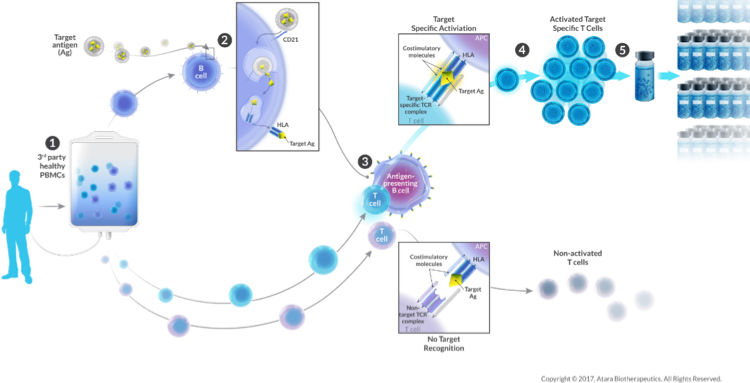

A pioneer in the T-cell immunotherapy space, Atara offers rapid delivery of Off-the-shelf bioengineered allogeneic T cells from donors with healthy immune function for the treatment of cancer, autoimmune and viral diseases. These can target cancerous and disease-causing cells with precision and eliminate them with minimal collateral cell damage. Most importantly, there is no need for lymphodepletion before treatment.

The company is leveraging its decade long clinical experience at Memorial Sloan Kettering (MSK) by using cell selection algorithm to identify the most appropriate T-Cell lines by matching key immune characteristics.

Image Source: https://www.atarabio.com/pipeline/preclinical-programs/

Image Source: https://www.atarabio.com/science-and-technology/next-generation-car-t-technologies/

Image Source: https://www.atarabio.com/wp-content/uploads/2017/08/AtaraBio_21Aug2017_web_CTLmanu-1.jpg